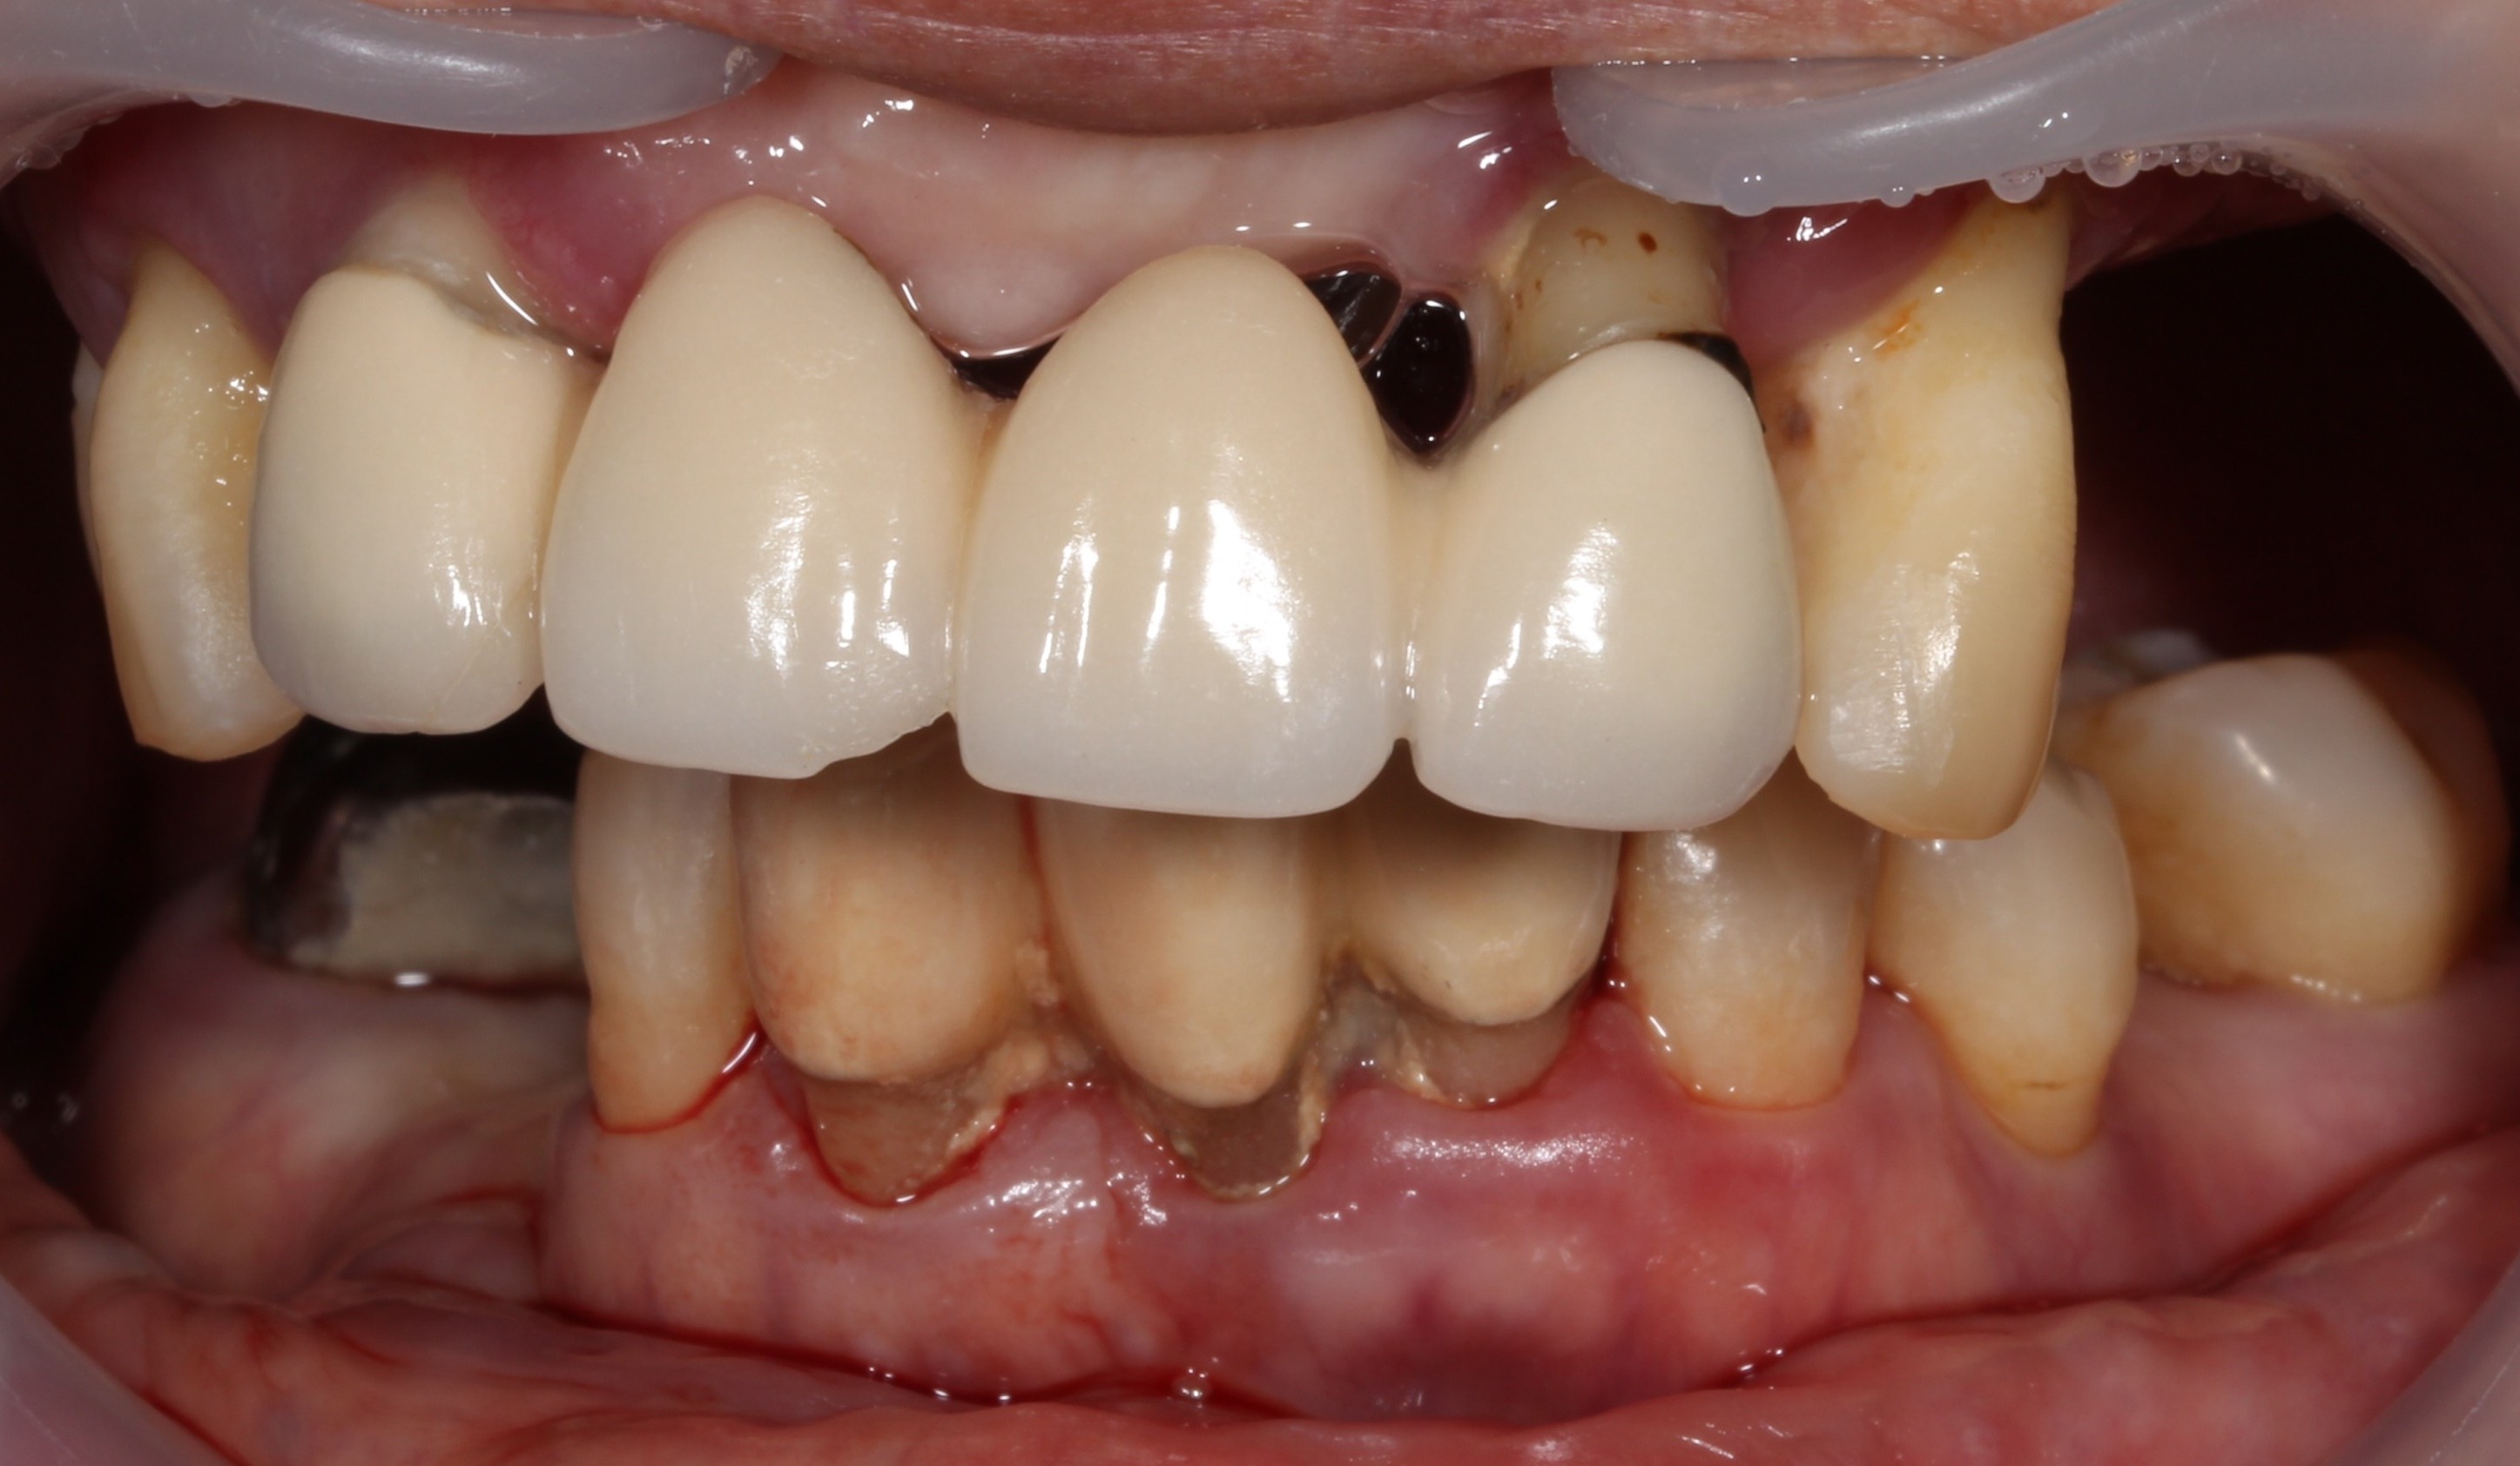

치료 전 임상사진

전반적으로 잇몸 건강이 무너진 상태에서 오랜 보철물 사용으로

전치부만 교합이 되는 상황이었습니다. 잇니 치아가 전체적으로 많이 흔들려 식사를 거의 하지 못하고 계셨습니다.